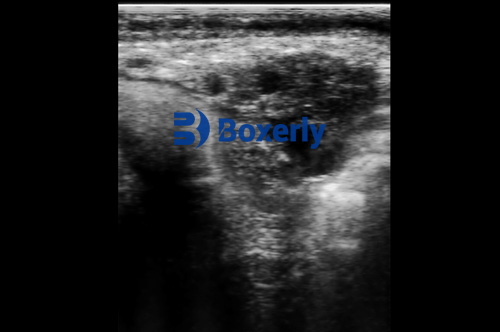

Ultrasound is frequently used to detect abnormal growths such as tumors or cysts in both domestic pets and farm animals. Unlike X-rays, which excel at showing bones, ultrasound is more effective for identifying soft-tissue masses and their characteristics, including shape, size, vascularity, and potential invasiveness.

In cases where a biopsy is required, ultrasound-guided fine-needle aspiration (FNA) enables precise needle placement, reducing trauma to the surrounding tissues and improving sample accuracy. This technique is particularly useful for targeting deep or irregularly shaped masses that are otherwise hard to localize.